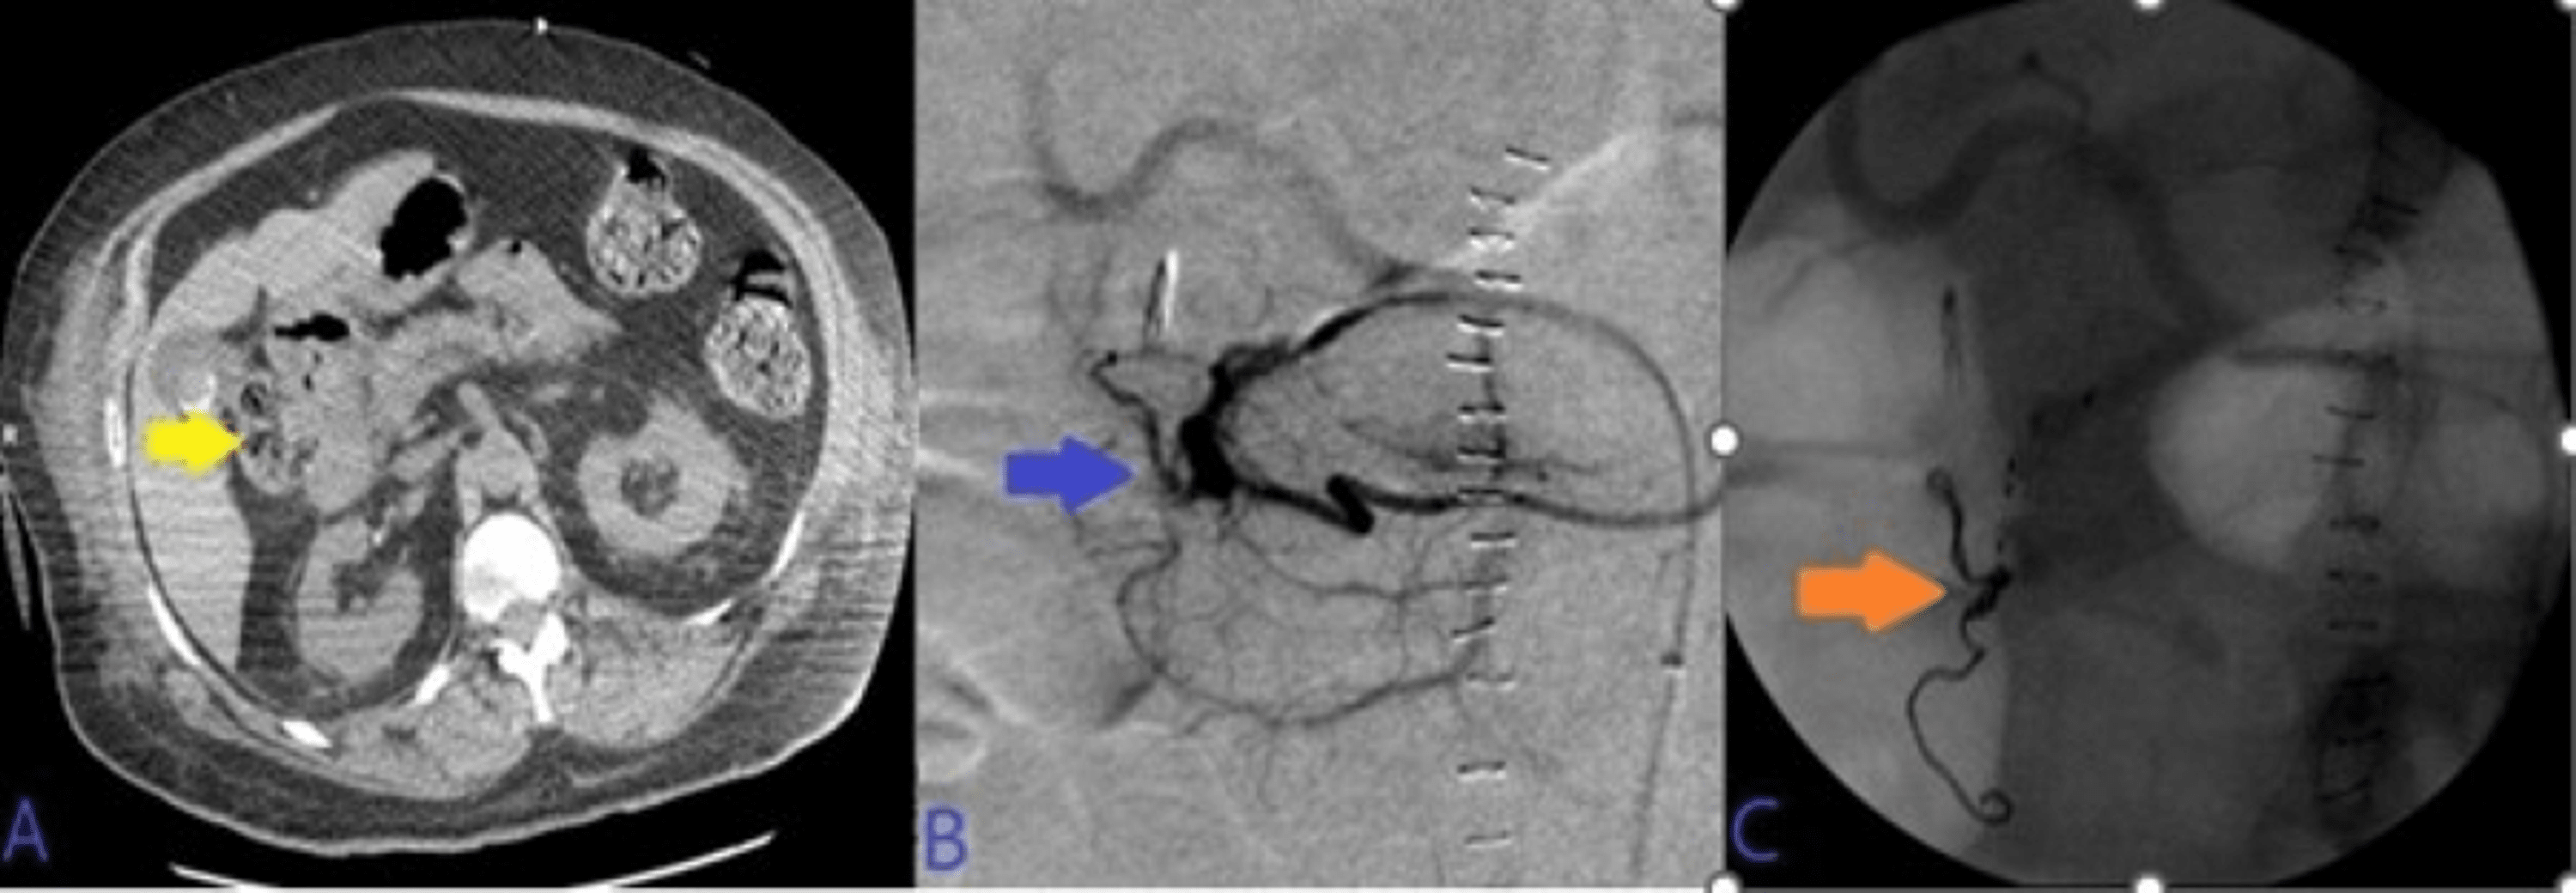

Embolization with two coils in the gastroduodenal artery (blue arrow Coil Embolization Duodenal Ulcer The primary clinical success rate was higher for duodenal ulcer (8 of 13 patients [62%]) and gastric cancer (3 of 5 patients. There is increased risk of gastric or duodenal infarction after embolotherapy in patients with previous extensive ugi surgery or. Endoscopic view of a large deep ulcer with a pulsatile visible vessel along the posterior aspect of the duodenal. Coil Embolization Duodenal Ulcer.

(AF) CT angiography (CTA) and digital subtraction angiography (DSA) of Coil Embolization Duodenal Ulcer Endoscopic view of a large deep ulcer with a pulsatile visible vessel along the posterior aspect of the duodenal bulb. The primary clinical success rate was higher for duodenal ulcer (8 of 13 patients [62%]) and gastric cancer (3 of 5 patients. There is increased risk of gastric or duodenal infarction after embolotherapy in patients with previous extensive ugi surgery. Coil Embolization Duodenal Ulcer.

Typical sandwich embolization in a 73yearold man with bleeding from a Coil Embolization Duodenal Ulcer Endoscopic view of a large deep ulcer with a pulsatile visible vessel along the posterior aspect of the duodenal bulb. The primary clinical success rate was higher for duodenal ulcer (8 of 13 patients [62%]) and gastric cancer (3 of 5 patients. There is increased risk of gastric or duodenal infarction after embolotherapy in patients with previous extensive ugi surgery. Coil Embolization Duodenal Ulcer.